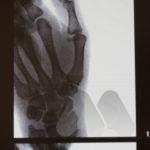

Carpal tunnel syndrome affects the median nerve that travels through a space that connects the forearm and hand at the front of the wrist. Pressure on the nerve, from many possible causes, can lead to a slowing of the electrical signals that supply sensation to the thumb, index and middle finger. It can lead to tingling and numbness in these fingers or the whole hand and can often be worse at night time.